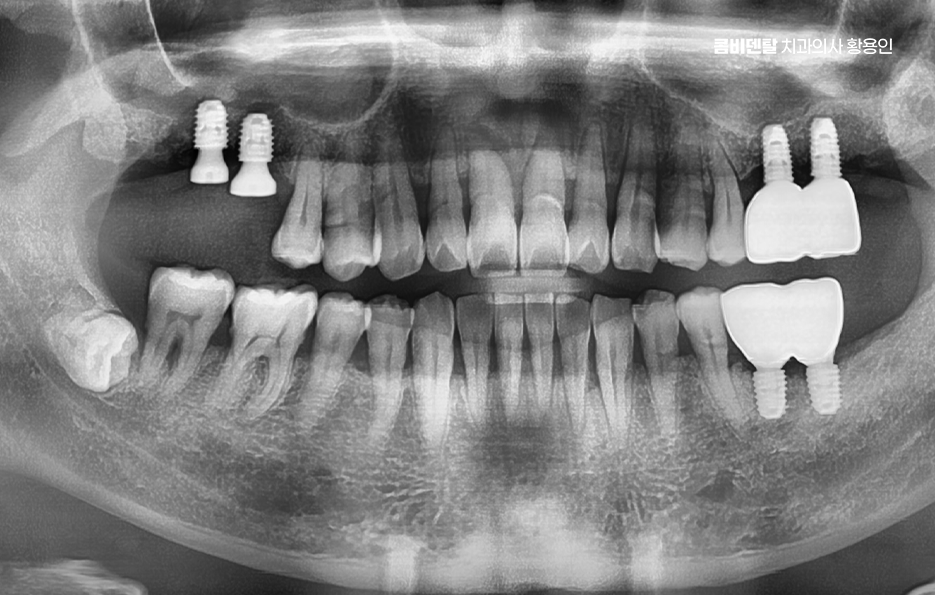

고령층에서 임플란트를 선택할 때 걱정하는 부분이 수술 자체이기도 한데 나이가 들면 뼈가 약해지고 당뇨, 고혈압, 골다공증 같은 전신질환을 겪고 있는 분들도 많다는 점에서 어르신 임플란트 지원 자체에 대해서도 혜택을 잘 받는 것이 중요하지만 노인 임플란트의 경우 현재 잇몸 뼈의 상태 뿐 아니라 전신건강에 대한 부분도 잘 체크해야 할 필요가 있는데요

그 뿐 아니라 예를 들어, 잇몸뼈가 너무 많이 녹아 있는 경우에는 뼈이식이나 상악동 거상술 같은 부가적인 치료가 필요한 경우도 많기 때문에 경험 많은 의료진과 치료 과정을 함께하는 것이 중요하며 장기적으로도 오래 함께할 치과를 잘 판단하실 필요가 있어요